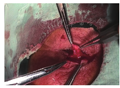

(3)利用剩余眼睑带蒂睑板结膜瓣转位重建眼睑后层:眼睑肿瘤切除后,更换手套及手术器械,在较大的剩余眼睑侧沿睑缘下4 mm切开睑板及睑结膜层,并向穹窿部彻底分离,形成一带蒂的睑板结膜瓣(图3),然后将睑板结膜瓣向眼睑缺损处转位,睑板部分用6-0可吸收线间断缝合于睑缘,两侧结膜部分缝合用9-0尼龙线间断缝合于两侧残余的睑板,重建眼睑内层(图4)。